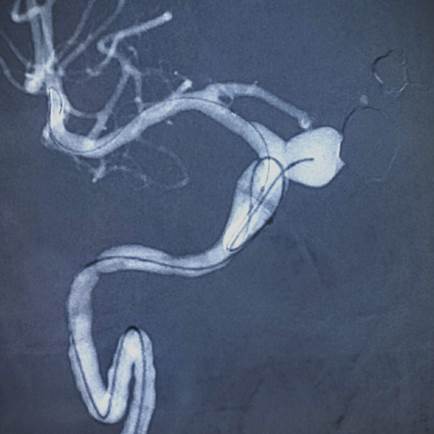

Aneurisma na artéria Carótida Interna Direita, medindo 9mm x 10mm

Liberação da mola Axium Prime